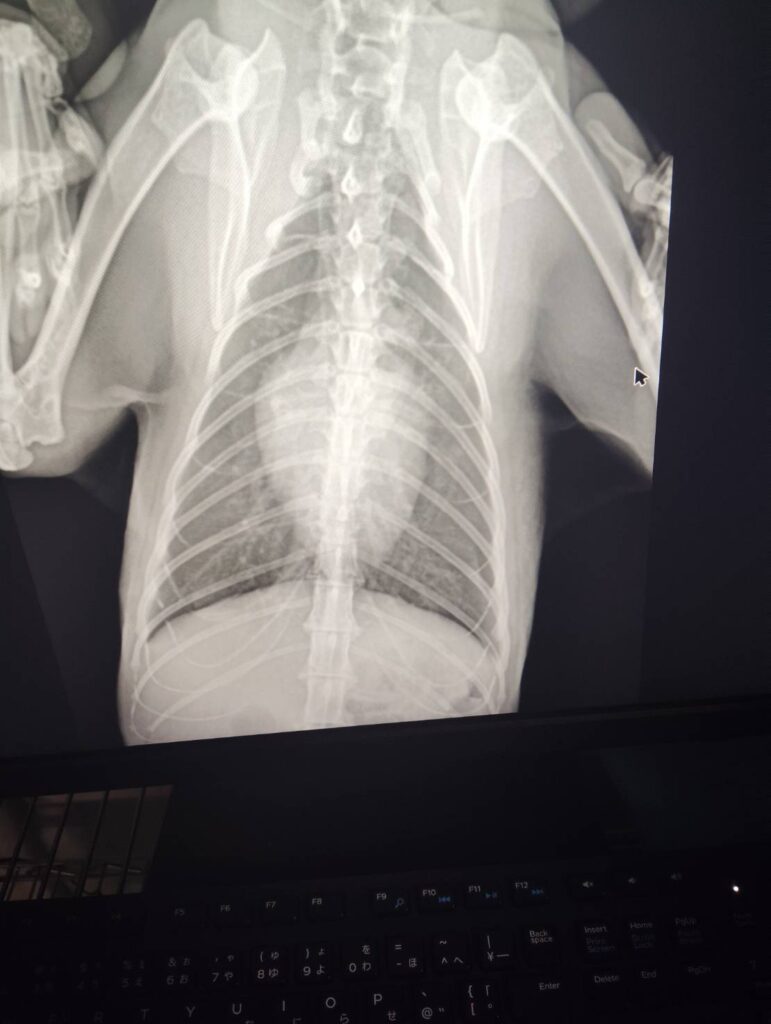

症例 猫 12歳 オス 来院理由 呼吸が早い、食欲がない 身体所見 呼吸回数96回 検査 【血液検査】 ・異常なし 【レントゲン検査】 ・心臓の輪郭不鮮明、心拡大 【心臓エコー検査】 ・左房拡大あり LAAO=1.8 ・心筋中隔壁 6mm 心筋自由壁8mm 診断 肥大型心筋症、肺水腫 方針 入院下で治療開始 3日後、状態良化のため、退院、内服開始し、定期検診の予定 実績に戻る 関連の症例を見る 循環器科 🫀犬の僧帽弁閉鎖不全症(心臓病)と肺水腫について